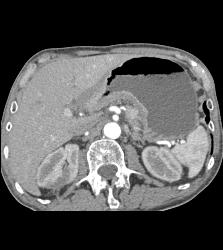

Antral Carcinoma With Celiac Nodes